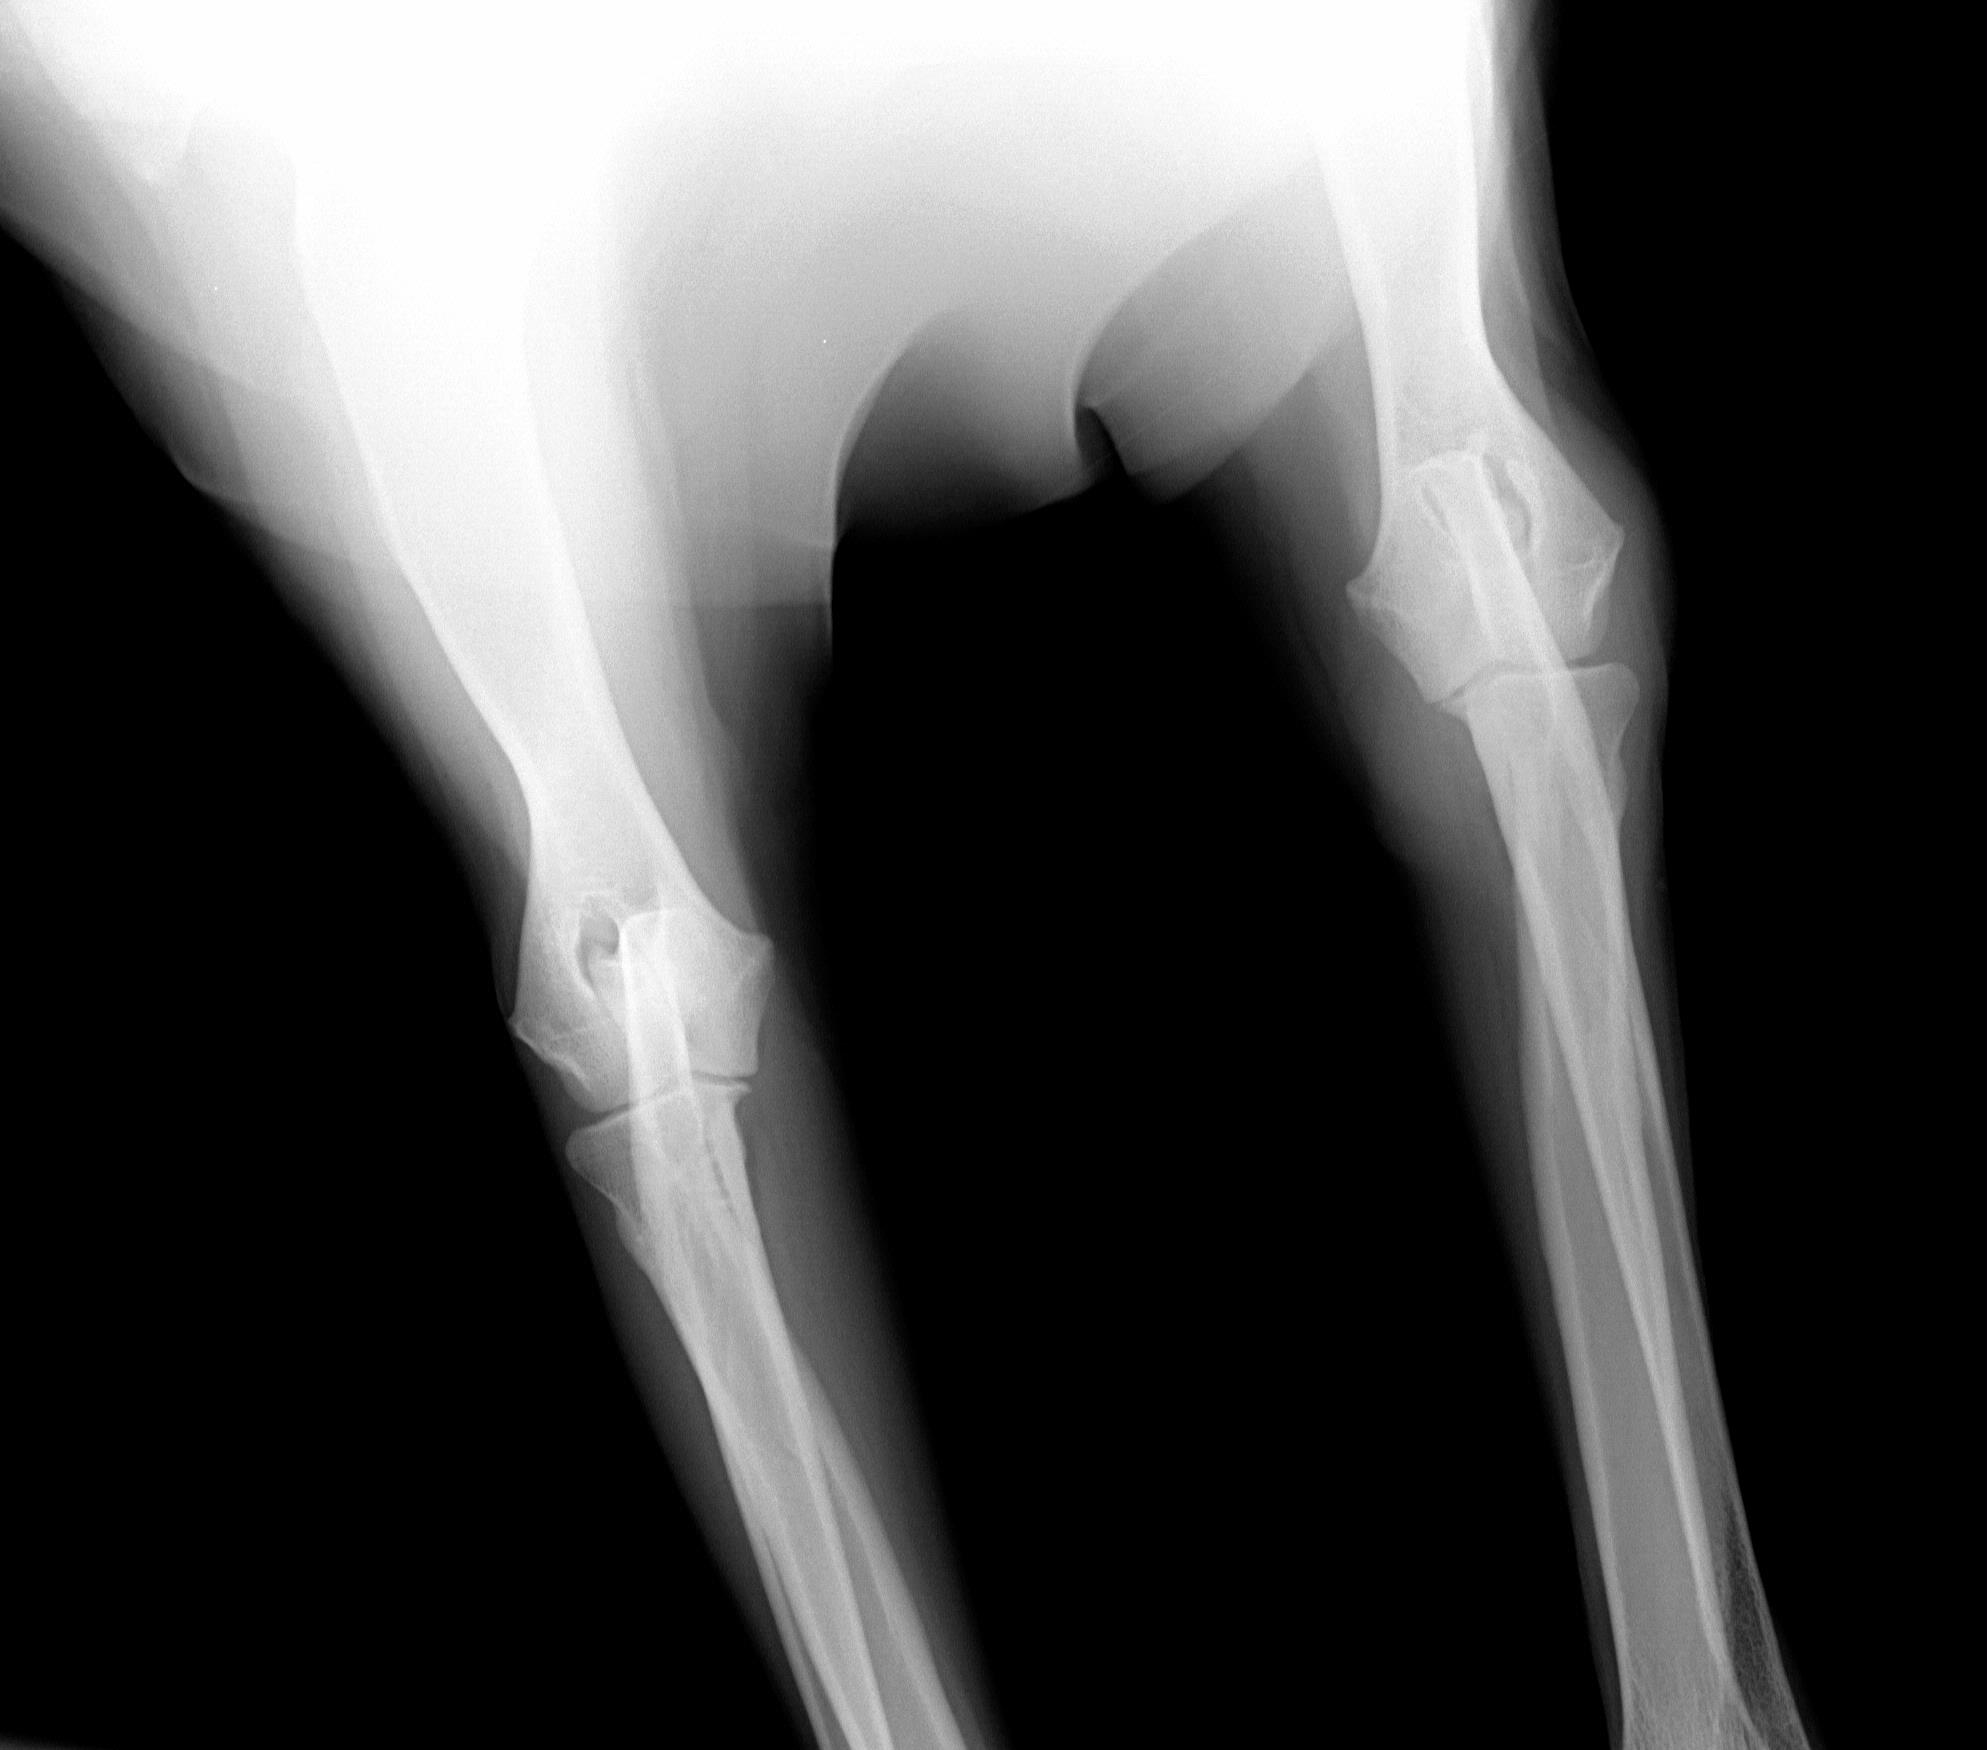

August 1, 2008 - X-rays taken at AMVC in Audubon, IA by Dr. Kristin Longfellow. She was not sedated for the x-rays. She was in slight discomfort in the area of the elbow if pressure was applied, at times seeing her trying to put weight on her toes, she was not in distress, but stiff and sore. We increased her metacam up to her weight limit.

August 4, 2008, Zoey was miserable, reluctance to go down two steps; favoring her front leg; licking it; swelling around elbow; very limited movement, etc. The swelling on the right elbow is not warm, nor cold to touch (unchanged). The swelling is hard/solid. Zoey was sleeping on her blanket (orthoped bed) on the floor without attempting to get on the bed with us at night. Zoey's eyes said she was miserable even though she was trying not to show it. The right leg is clearly marked on the xrays. She was conscious and not sedated for the xrays.

Zoey seen August 1, 2008 by Dr. Kristin Longfellow

due to limping and swelling of the front right forearm/elbow/shoulder area.

X-rays below.

On July 3, 2008, after Zoey finished her pig ear she was chasing her tail and caught the corner of the wall and never recovered from her injuries.The xray was taken 2/13/09

The following xrays were taken August 2008.